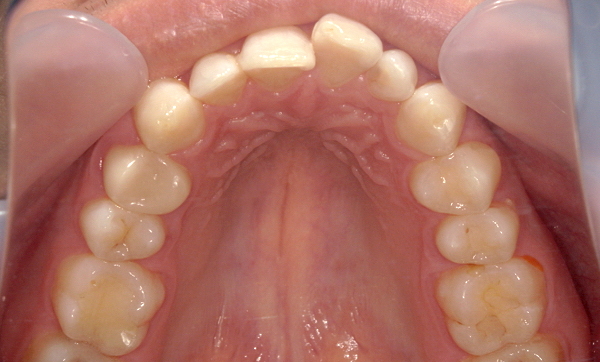

症例_007 「上下の前歯」症例

治療期間:11ヶ月金額:54万円+税40代女性捻転歯

Before | After |